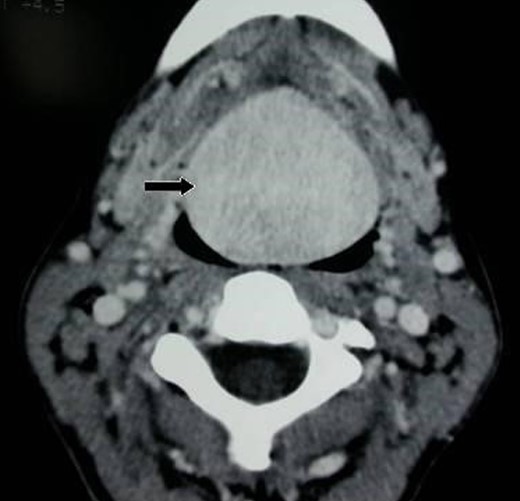

We report a case of a 32-year-old-lady who presented to our department complaining of dyspnea, dysphagia, hot potato voice and decreased appetite. Her symptoms exacerbated as she got pregnant 4 years prior to presentation. Her medical and surgical records were unremarkable. Physical examination disclosed a large, incompressible, non-tender midline mass at the base of the tongue extending posterio-inferiorly. Fibroptic nasolaryngoscopy demonstrated extension of the mass down to the valleculae with a wide base and an eventual narrowing of the hypopharynx. Blood tests were strictly normal except for hypothyroidism (TSH 18 uIU/dl, FT4 0.85 pg/dl). Computed tomographic (CT) scan depicted a large enhancing, homogeneous and well demarcated mass at the tongue base region (Fig. 1). Scintigraphy scan revealed increased uptake in that region confirming the ectopic lingual nature of thyroid tissue. Patient was scheduled for complete surgical resection after she rendered euthyroid. By adopting the external cervical approach, a midline mandibular split combined with lateral pharyngotomy provided adequate exposure and good bleeding control during the operation. Then en-block resection of the mass performed (Fig. 2). Postoperative course was uneventful. On pathological examination the specimen weighed 32 g and measured 6.0 × 4.0 cm2. Microscopically, the nodule revealed to be a minimally invasive follicular carcinoma arising in a lingual ectopic thyroid tissue (Fig. 3). Patient received radioactive I 131 as a complementary treatment. Follow up after 6 months revealed a firmly normal examination.

Axial computed tomography-scan with contrast showing a large 6 × 4 × 3.5 cm3 lingual tumor (black arrow).